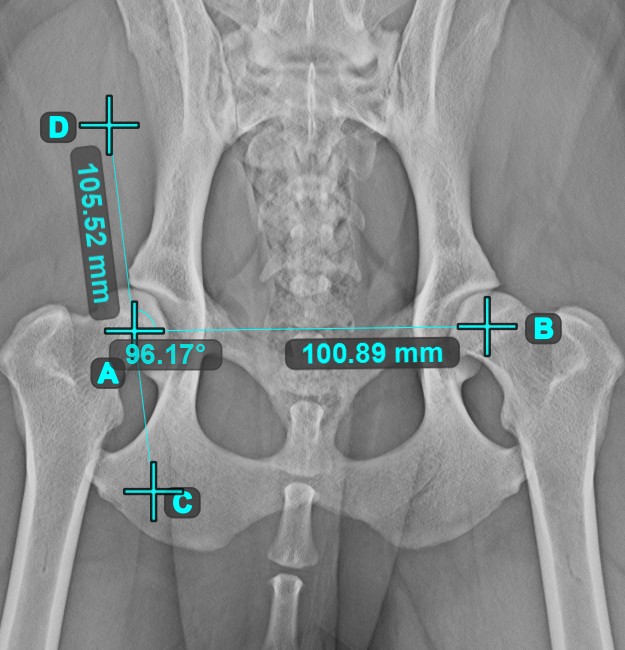

Válassza ki az eszközt a bal oldali eszköztárból, és rendelje hozzá az egyik elérhető egérgombhoz. A jelenetben már meglévő vonalak közül kezdje az első vonal kiválasztásával , vagy helyezze el a kezdő- és végpontot a vonal létrehozásához. Ismételje meg ugyanezeket a lépéseket a mérés második vonalánál. A két vonal közötti szög automatikusan kiszámításra kerül.

Módosítsa mindkét vonal kezdő- és végpontját az Elem kiválasztása/mozgatása eszközzel. A két vonal közötti szöget automatikusan újrakalkulálja a rendszer.

Szög 3 pontból¶

A Szög 3 pontból eszköz egyszerű és hatékony módja annak, hogy egy szöget mindössze három pont alapján számítson ki.

Kezdje az eszköz kiválasztásával a bal oldali eszköztárból, és rendelje hozzá az egyik elérhető egérgombhoz. Helyezze el a szög kezdeti oldalának kezdőpontját, a csúcsot és a szög végoldalának végpontját, vagy válassza ki a pontokat a jelenetből. A szög oldalai automatikusan létrejönnek, így a vonalak közötti szög kiszámításra kerül.

Módosítsa a három pont helyzetét a szög ívének megváltoztatásához az Elem kiválasztása/mozgatása eszközzel.